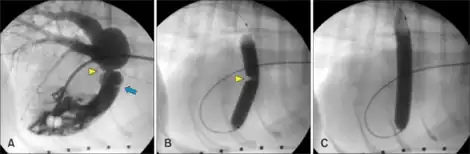

| a)Pulmonary valve blue arrow and supravalvular pulmonic stenosis yellow arrowhead b)contrast solution across the stenotic lesion yellow arrowhead c) full inflation of balloon | |